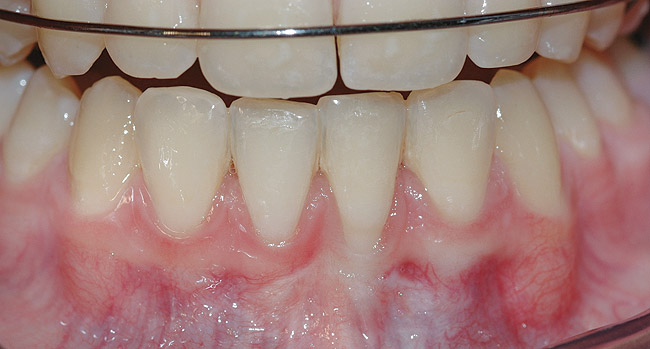

CASE 1 Fig 2. Pre-treatment clinical view of a 28-year-old patient with Miller Class I recession of the lower left central incisor treated with conservative SPT.

Figure 2

Fig 3. Two-year follow-up of same patient shows spontaneous root coverage.

Figure 3

When the tooth is properly aligned within the arch, treatment is managed with reference to Miller’s classification.7 Because most post-orthodontic GR cases are classified as Miller Class I and II defects, the authors focus on the management of these two classes only, and within the scope of this article, Miller Class III and IV defects are not addressed. Surgical root coverage of both Miller Class I and II defects is one treatment choice. However, in Miller Class I cases, a conservative approach can be considered, as well. Such an approach consists of supportive periodontal treatment (SPT)—professional periodic deposit removal every 2 to 3 months during a 1- to 2-year period. The authors’ clinical experience shows that spontaneous root coverage may occur following this conservative approach, particularly in young patients (Figure 2 and Figure 3). Similar results have been reported in a 3-year prospective study in which recession defects healed spontaneously following improvement in oral hygiene standards in children.30 In cases in which no root coverage is observed at the end of the follow-up period, surgical root coverage can be considered.